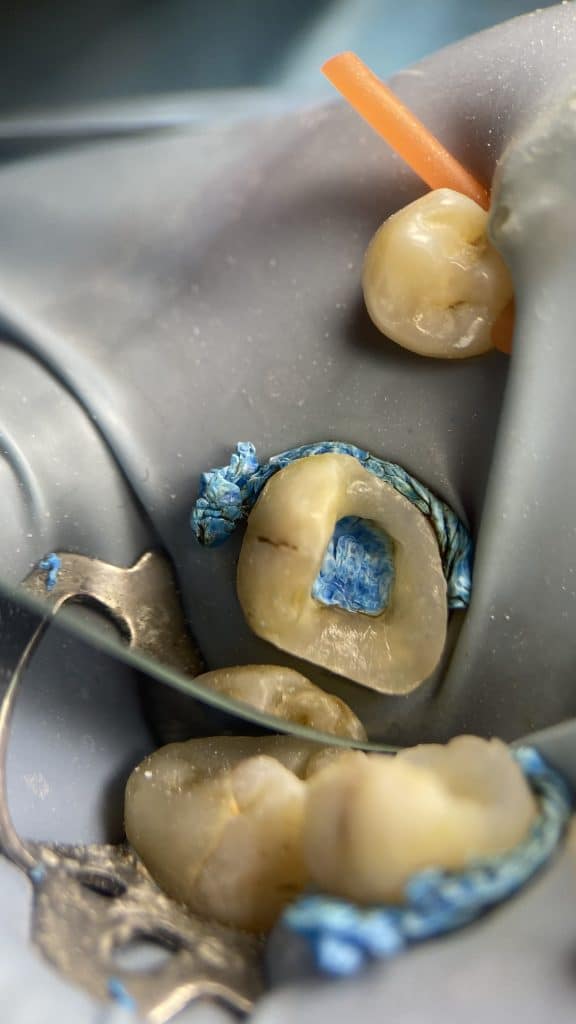

But thanks to the good irrigation &activation that made the bioceramic sealer close the apex

Also the buccal wall fractured between the visit

And the tooth will restored with indirect overly

sorry for mobile photography